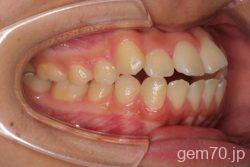

症状:開咬装置:セラミックブラケット | 抜歯世代:10代 | 高校生

診断)開咬

使用装置)マルチブラケット装置

治療方法)抜歯 4|4/4|4